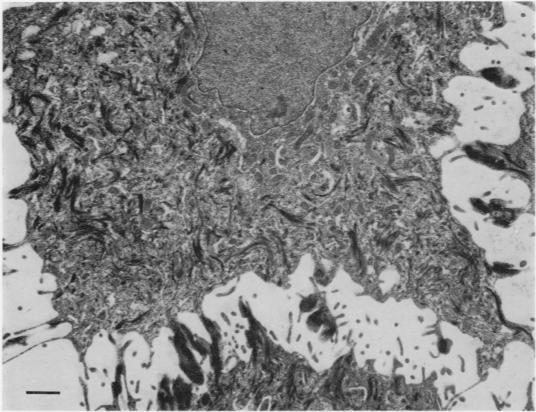

A quantitative comparison between normal and carcinomatous squamous epithelia of the uterine cervix.

The object of this study was to measure some of the differences between normal squamous epithelial cells and cells from invasive squamous carcinoma of the uterine cervix. A total of 107 patients were studied; only those specimens which when assessed by a histopathologist were thought to show classic normal features or undoubted invasive carcinoma were included in the quantitative analysis. In addition, any specimens which at the electron microscope level, showed faulty sampling or preparation were discarded, leaving us with 16 carcinoma and 15 normal specimens for detailed study.The nuclei of tumour cells had a greater area than those of normal cells; histograms of the size distribution of nuclei showed a distinctly different pattern in the 2 groups. Tumour cells had fewer ribosomes in each cubic micron of cytoplasm than had the normal cells and showed a reduction in the amount of intercellular space; in addition, the malignant cells had a smaller surface density and fewer tonofibrils in their cytoplasm. Some tumour cells had a smaller percentage of cell membrane specialized as desmosomes than the corresponding normal cells but all tumour cells had desmosomes of shorter length than normal.Discriminatory analysis, carried out with the help of a computer, allowed all of these variables to be assessed with respect to each other in order to arrive at a numerical score for each specimen. When expressed graphically, these scores showed that the populations of normal and carcinomatous cells fell into 2 separate groups. The significance of these results is discussed.